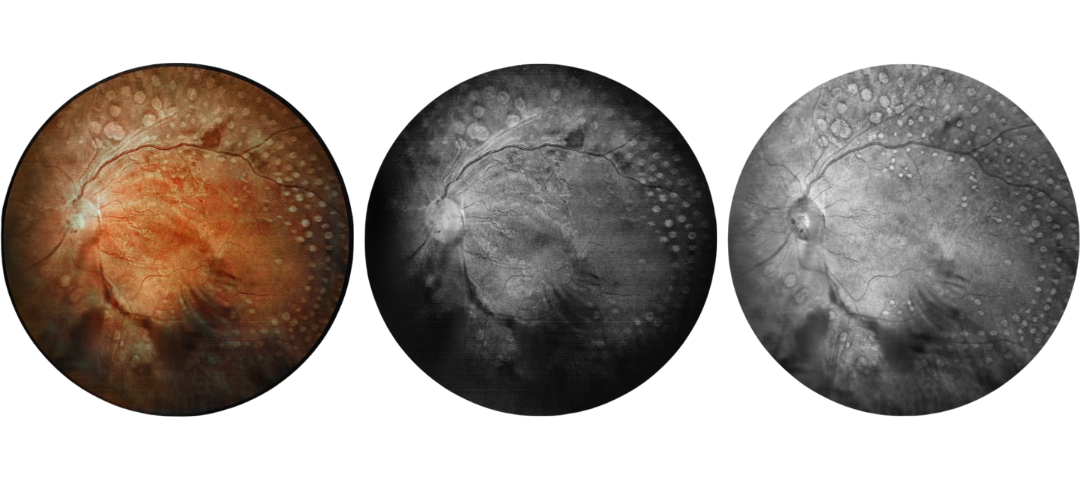

Fundus Cases Display

Our SLO makes fundus examination easier for you, capturing ultra-clear and wide-angle images of the retina and choroid, and then synthesizing color fundus images to present a rich picture of the fundus status.

Diabetic retinopathy: vascular abnormalities, bleeding spots, and post-photocoagulation

Diabetic retinopathy: bleeding, exudation and choroidal vascular abnormalities